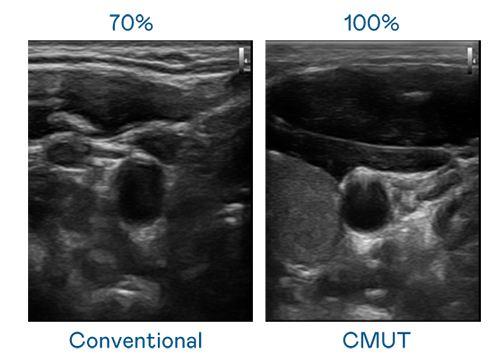

CMUT 技术是一种用电容式微机电元件来产生超音波讯号的技术。与传统 PZT 压电式技术相比,CMUT 频宽增加 30%,更宽频的超音波讯号让影像解析度大幅提升,是实现高影像品质医疗超音波扫描、促进精准医疗发展的关键技术。

大频宽带来超清晰影像

超音波影像的解析度高低,首先取决于探头能发出的讯号频宽。法国空姐2019多塞尔航空星辰影院 CMUT 可提供高清晰的超音波讯号,提供高频宽、高灵敏度、影像纹理细节更高的超音波影像,协助医护人员缩短影像判读时间及利用精准的医疗影像进行诊断。